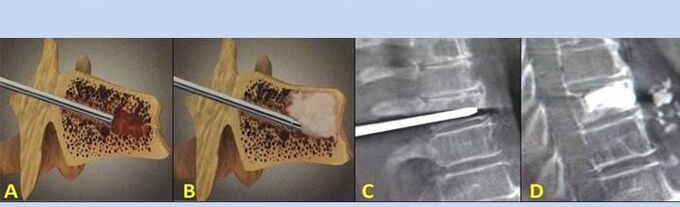

- Nukleoplastika – uklanjanje jezgre intervertebralnog diska. Operacijom se smanjuje pritisak na živčane završetke.

- Punkcijska vertebroplastika – metoda stabilizacije kralježaka. Tijekom postupka liječnik ispunjava šupljine kralježnice koštanim cementom.